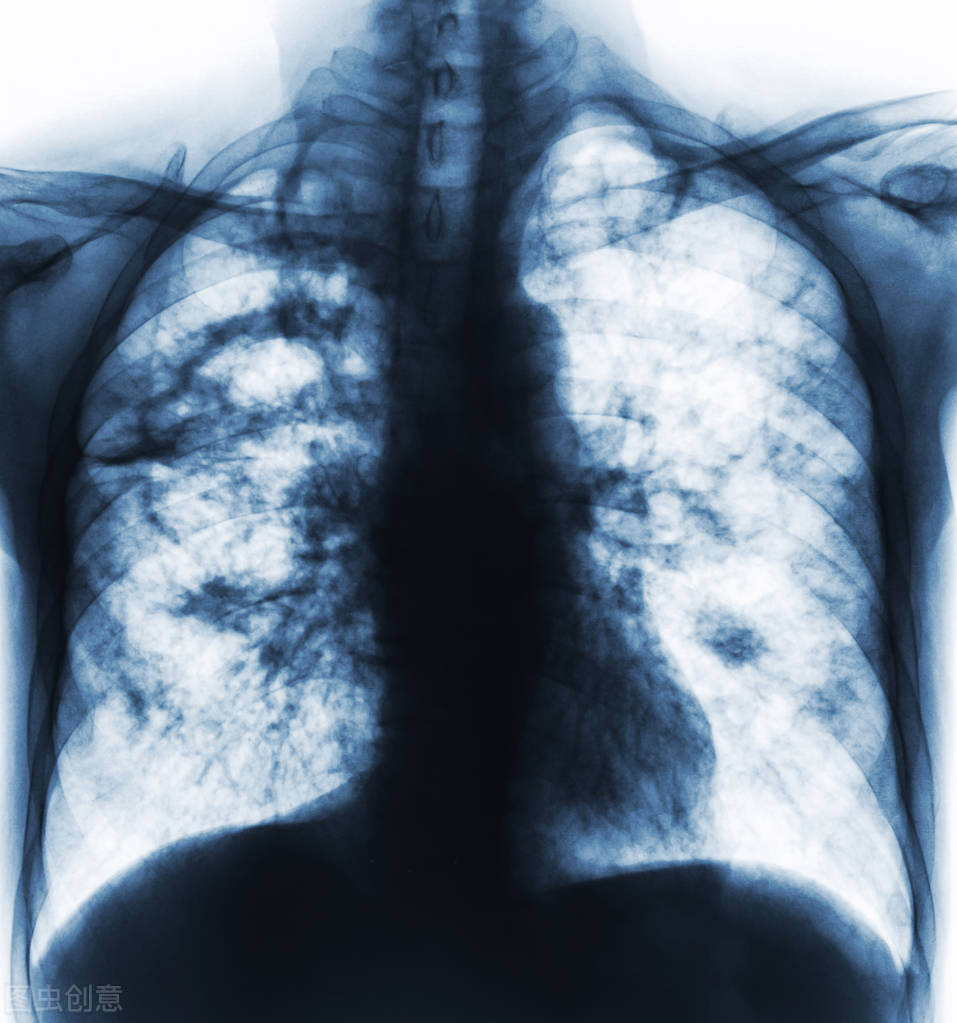

通常意义上讲,肺炎就是发生在肺部的炎症,这种炎症可以发生在肺部的任何地方。

比如终末气道,肺泡以及肺间质,这些地方都是炎症好发的部位。

在医院,医生往往会做一些检查,常见的检查包括血常规,放射线。

当然,如果觉得必要,还会考虑做肺部ct来判断疾病。